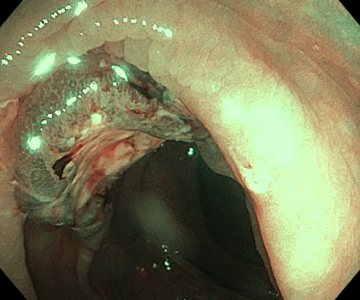

Пациент М, 40 лет. Беспокоили боли в брюшной полости. По ОАК -эозинофилия. Подготовка к колоноскопии идеальная, при исследовании выявили гельминта-аскариду, извлекли, аскарида была еще живая.

Пациент К, 75 лет, в 2018 году оперирован по поводу опухоли нисходящей ободочной кишки. Ежегодно проходил колоноскопии (не в нашей клинике), в июне 2024 года при обследовании в «Здоровье» выявили образование в восходящей ободочной кишке (от момента предыдущей колоноскопии (не у нас) полгода). Прооперирован.

Пациент О. 58 дет на протяжении нескольких лет наблюдалась по месту жительства с образованием желудка, по биопсии -гиперпластический полип. При обследовании в нашей клинике гистологически -тубулярная аденома с умеренной дисплазией и одним фрагментом тяжелой дисплазии (а это считается ранним раком), удален.

Пациент Ч 70 лет, ранний рак пищевода, направлен на лучевую терапию.